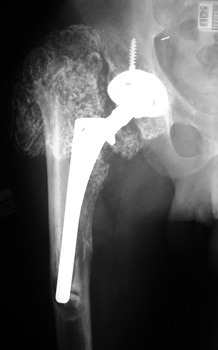

HETEROTOPIC BONE FORMATION adjacent to loose femoral component, plain film and CT